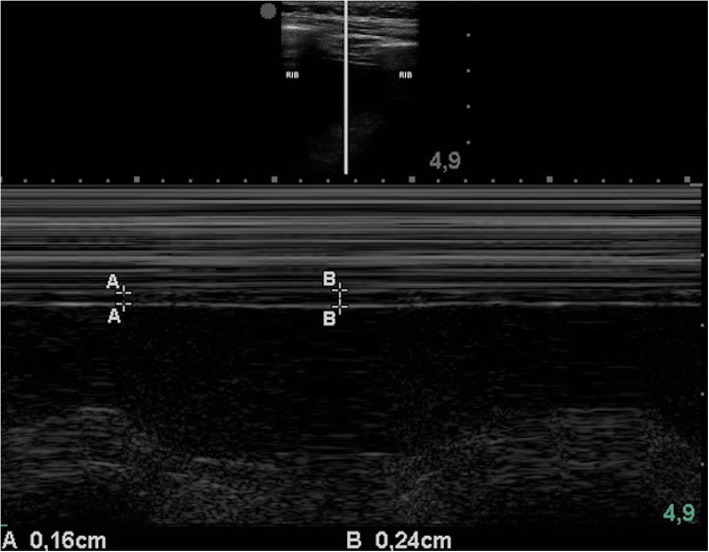

To measure the thickening fraction, a high-frequency probe (7–18 MHz) is placed in the anterior axillary line, trying to obtain the image of the diaphragm between two ribs usually between the seventh and the eighth or the eighth and the ninth. Once the diaphragm is located, a cut is made in M mode; the maximum diaphragmatic thickness is obtained during inspiration, and the minimum during expiration and the thickening fraction is calculated using the formula: [(inspiratory thickness − expiratory thickness)/expiratory thickness]. A value below 0.2 is considered a diagnosis of diaphragmatic dysfunction (Fig. 1) [2], and 0.26 was identified as the optimal threshold value to predict extubation failure [5].

Fig. 1.

Diaphragmatic M mode. This image shows an increase in diaphragmatic thickness during inspiration. The lines marked with “A” show thickness during expiration, and the lines marked with “B,” the maximum thickness during inspiration